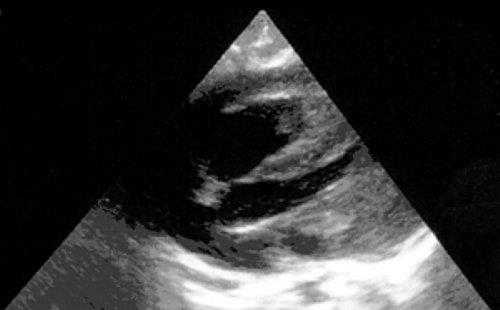

Миксомы построены из перегруженных липидами многоядерных клеток, погруженных в миксоидную строму, богатую гликозаминогликанами. Клетки располагаются группами вокруг сосудов. В 10% случаев в опухоли обнаруживаются депозиты кальция. Миксомы свойственны подросткам (рис. 3), у детей встречаются редко. Более 80% всех миксом исходят из межпредсердной перегородки и митрального клапана. Миксома может быть как спорадической (90% случаев), так и семейной опухолью (10%), наследуемой аутосомно-доминантно (миксомный синдром) в рамках синдрома Карнея [3, 4]. При семейном варианте миксома обычно множественная и склонна к рецидивированию [5, 6].

Рис. 3. Миксома левого предсердия.

а) 1 и 2 - стенка аорты, 3 - миксома.

б) Макропрепарат удаленной миксомы.